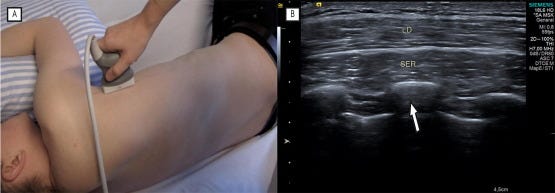

Músculo serrato anterior.

A) El transductor se colocó por detrás de la línea axilar posterior, alineado con la axila. En esta posición se visualizan la segunda costilla (nivel 1), la tercera costilla (nivel 2) y la cuarta costilla (nivel 3), respectivamente, desde la axila hacia el centro de la imagen, girando el transductor de modo que la costilla se muestre en corte transversal. Al realizar esta maniobra, la porción craneal del transductor se orientó hacia anterior.

B) Imagen ecográfica (US) del músculo serrato anterior, con el músculo dorsal ancho (LD) situado superficialmente y las costillas (flecha blanca) en un plano profundo.